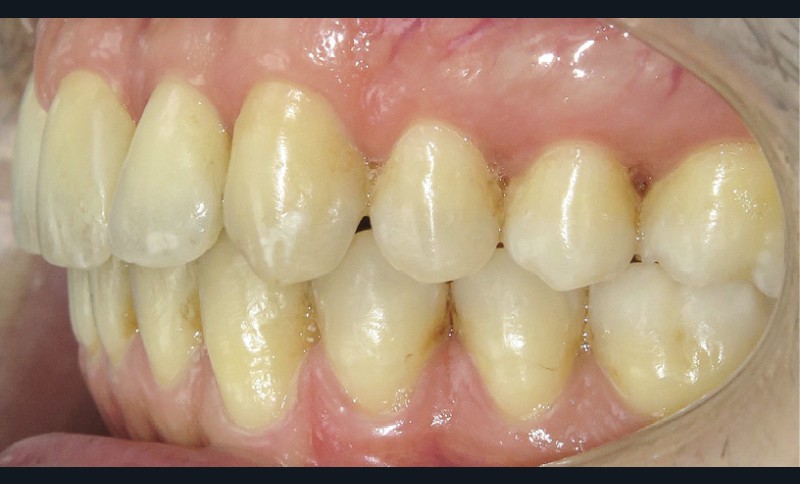

Diagnostic (fig. 1a-i)

Le patient consulte initialement pour des défauts d’alignement. L’examen clinique confirme l’existence d’un encombrement antérieur bimaxillaire, mais révèle aussi la présence d’une Classe II dentaire sévère, d’une exoclusion de la 27 et de troubles parodontaux (peu ou absence de papilles inter-dentaires). Sur le plan squelettique, le patient est relativement équilibré avec un profil harmonieux.